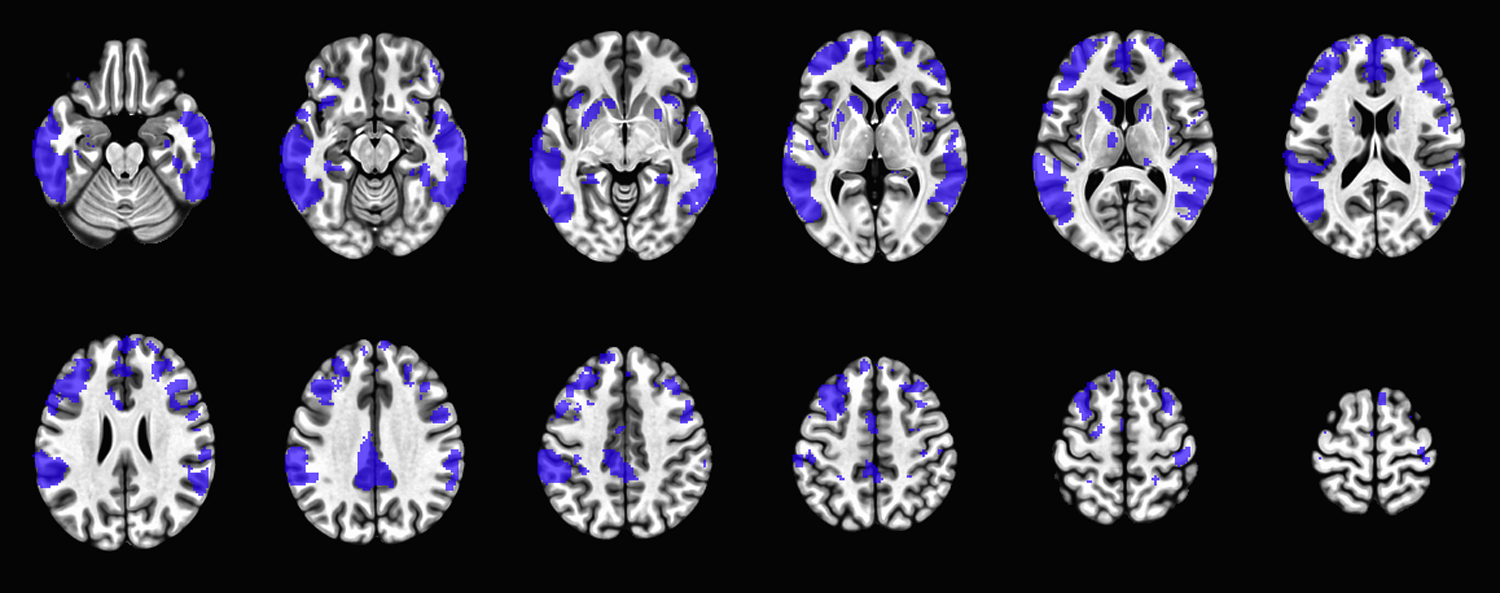

Abstract Image